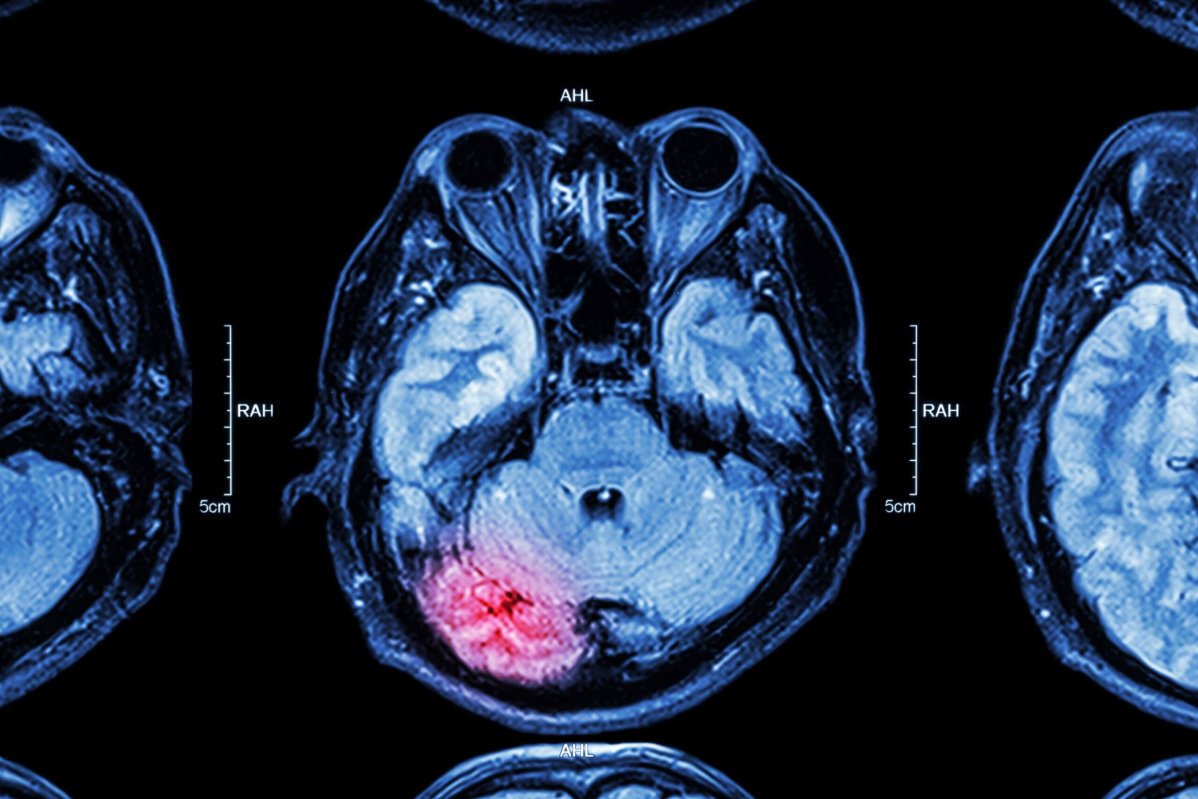

Методом вибору для первинної діагностики черепно-мозкової травми є комп'ютерна томографія головного мозку. Дослідження дозволяє швидко виявити внутрішньочерепні гематоми, забої мозкової тканини, переломи кісток черепа та ознаки компресії мозкових структур.

Магнітно-резонансна томографія використовується для детальнішої оцінки ушкоджень мозкової тканини, зокрема при підозрі на дифузне аксональне ушкодження або невеликі внутрішньомозкові крововиливи.